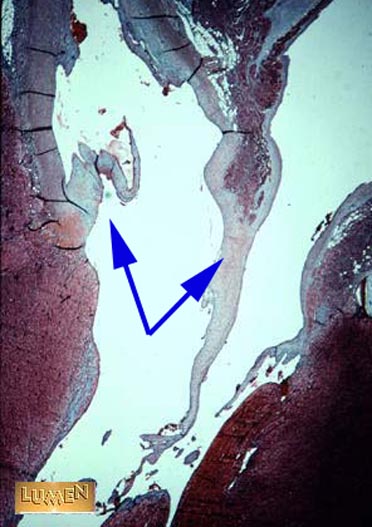

Name the structure indicated by the arrows.

Semilunar valves